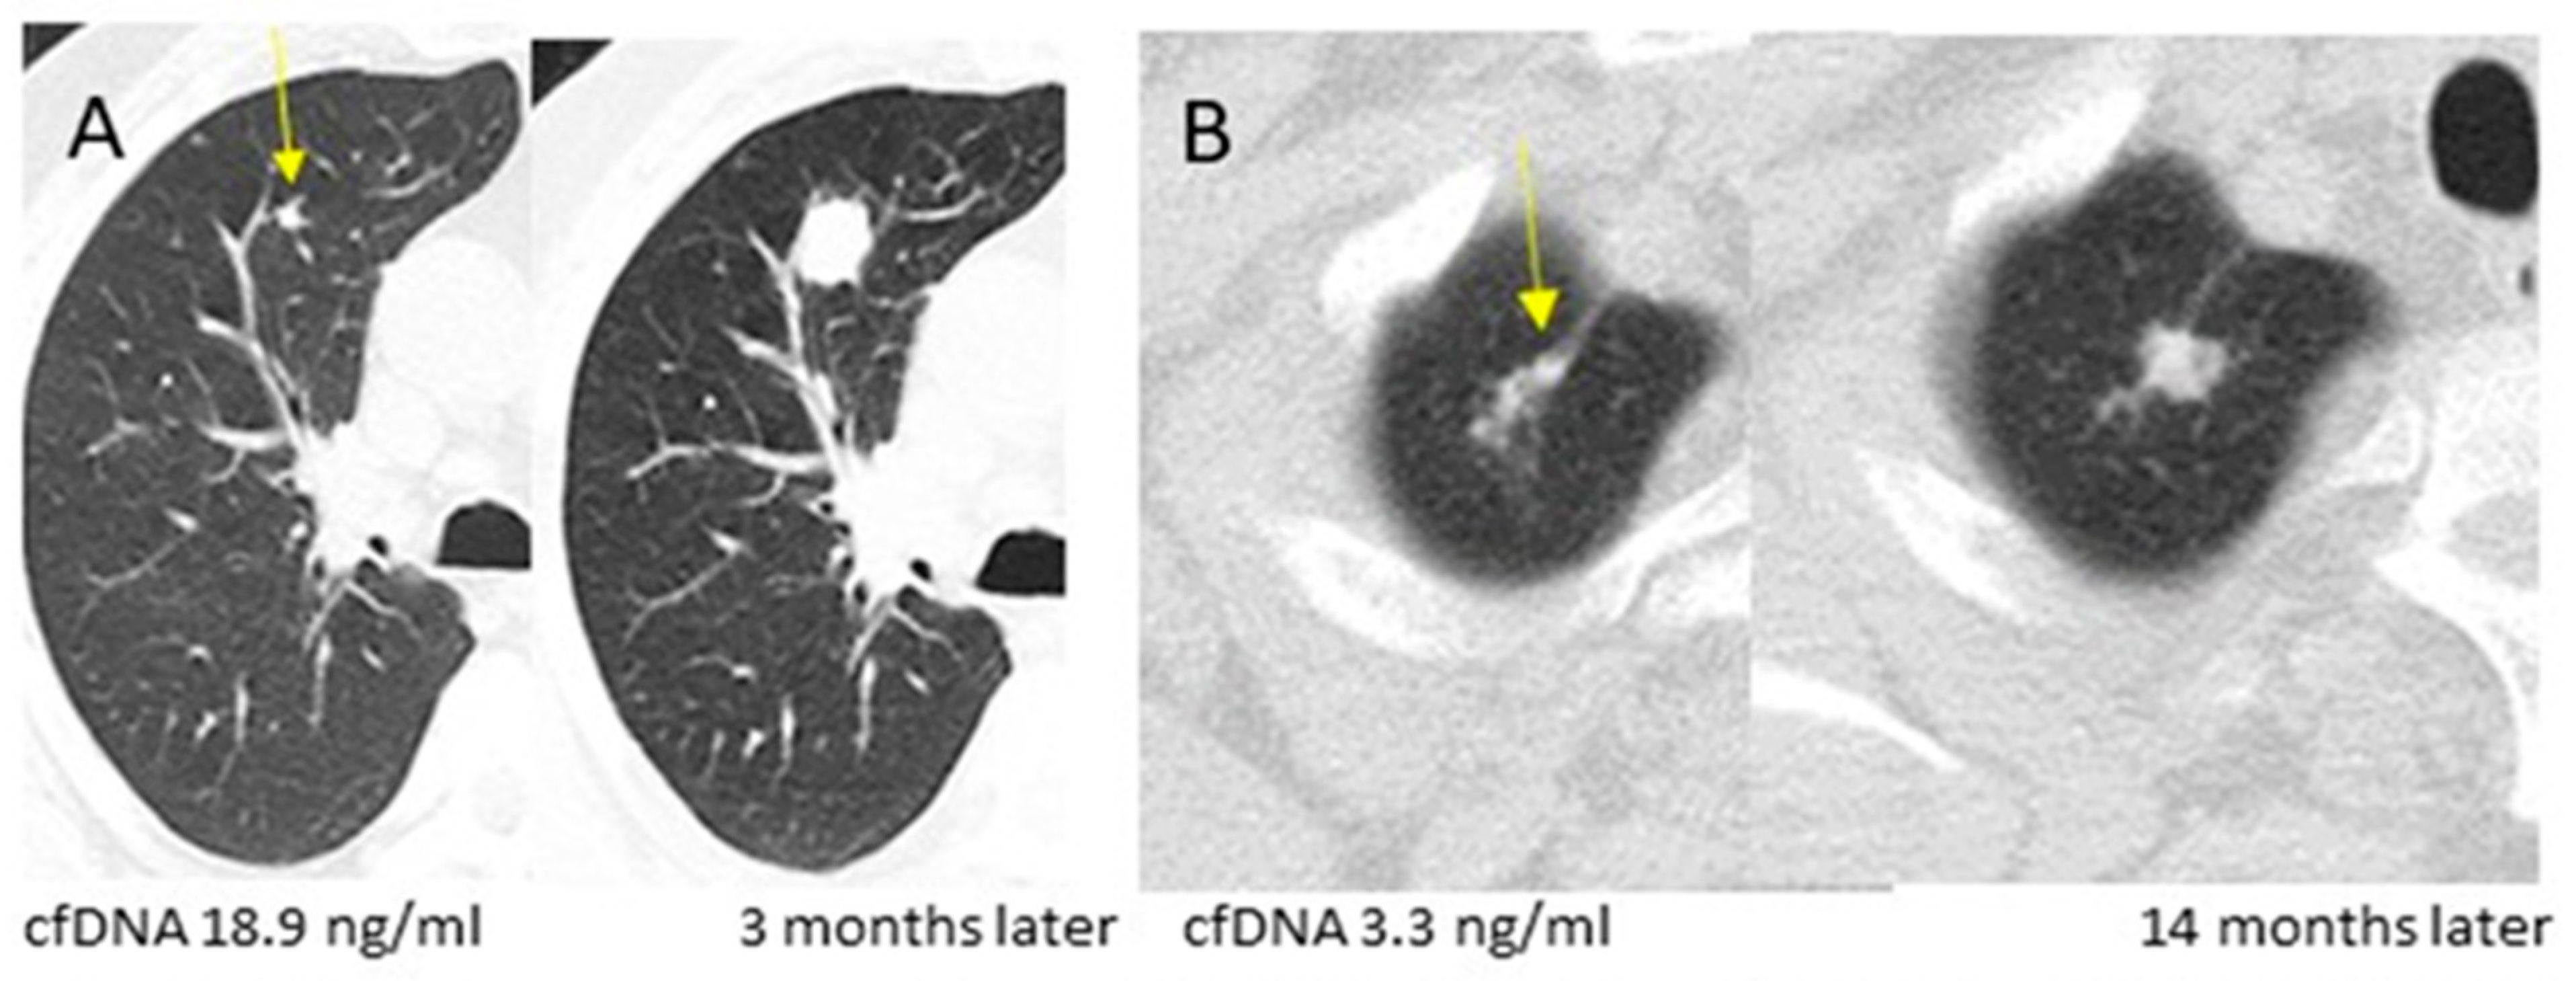

| mean | 3.3 | 18.8 | 4.8 | <0.001 |

| category: n (%) | ||||

| <3.15 | 71 (65.7%) | 3 (17.7%) | 3 (25.0%) | |

| [3.15–5) | 21 (19.4%) | 2 (11.8%) | 5 (41.7%) | |

| ≥5 | 16 (14.8%) | 12 (70.6%) | 4 (33.3%) | <0.001 |